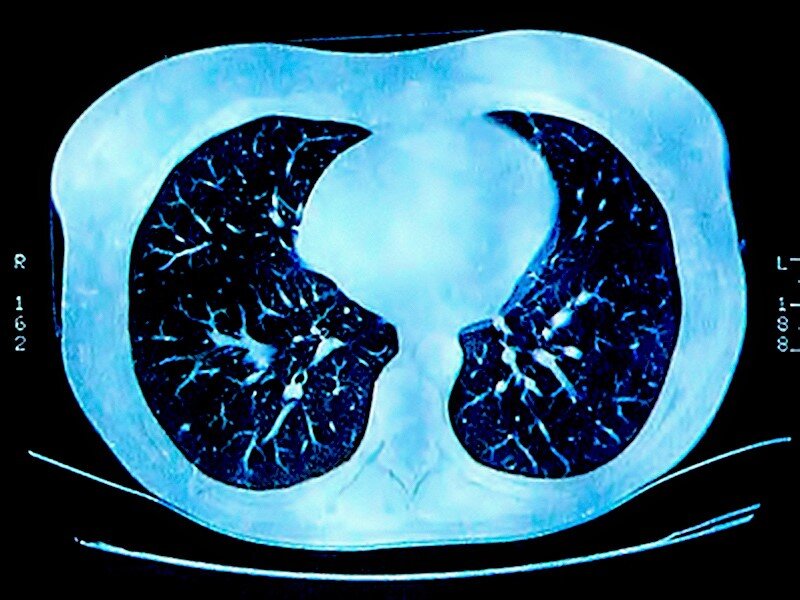

Органы в человеческом теле стареют по-разному, и часто их возраст вообще не соответствует биологическому возрасту человека. Сколько лет легким?

Вы можете быть удивлены, но в основном их возраст от двух до трех недель! Клетки легких постоянно обновляются. Однако с курильщиками все иначе.

В легких содержатся разные клетки, которые по-разному регенерируют. Например, альвеолы, необходимые для кислородного и газообмена, регенерируются в течение года, а клетки на поверхности легких заменяются каждые две или три недели. У курильщиков, однако, их регенерация затрудняется эмфиземой, которая начинается с разрушения альвеол, в результате чего в легких образуются постоянные дыры.